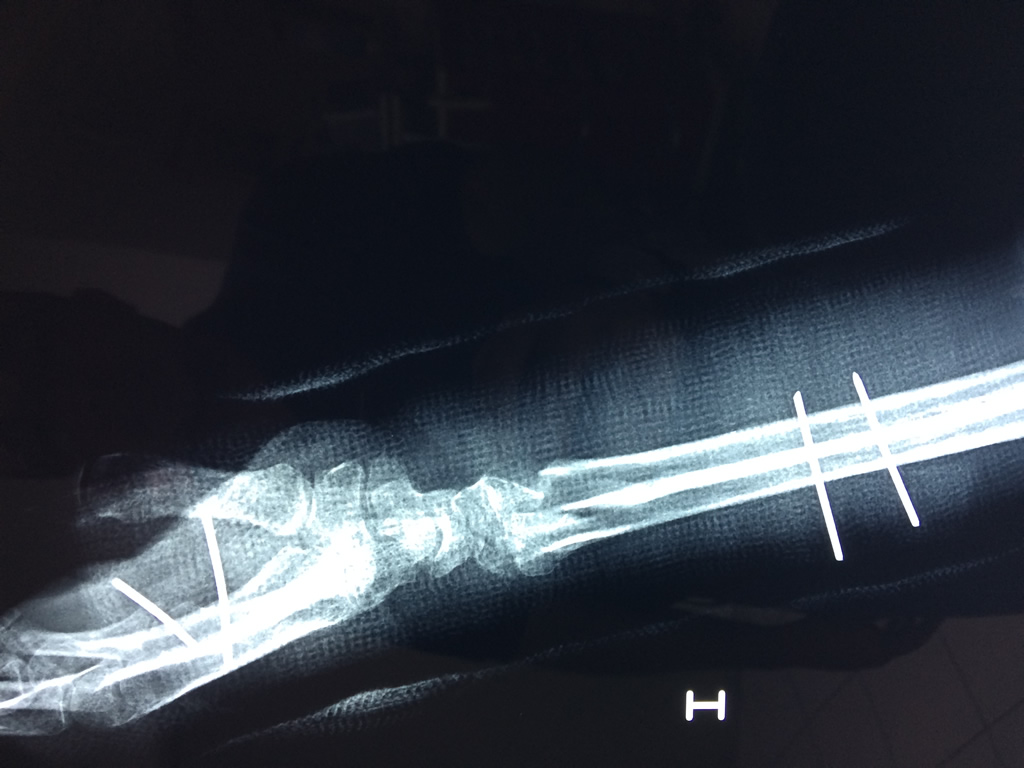

Cirugias en El Salvador - Cirugías de Muñecas y Manos

Los procedimientos más comunes en cirugía de la mano son aquellos destinados a reparar traumatismos, incluyendo lesiones de tendones, nervios, vasos sanguíneos, y articulaciones; huesos fracturados; y quemaduras, cortes, y otros daños de la piel.